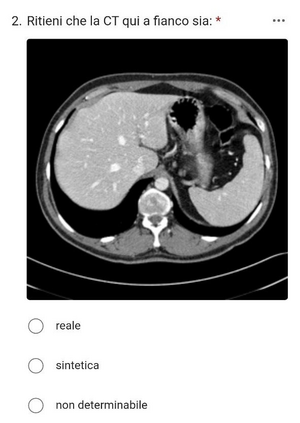

In many clinical settings, the use of both Computed Tomography (CT) and Magnetic Resonance (MRI) is necessary to pursue a thorough understanding of the patient's anatomy and to plan a suitable therapeutical strategy; this is often the case in MRI-based radiotherapy, where CT is always necessary to prepare the dose delivery, as it provides the essential information about the radiation absorption properties of the tissues. Sometimes, MRI is preferred to contour the target volumes. However, this approach is often not the most efficient, as it is more expensive, time-consuming and, most importantly, stressful for the patients. To overcome this issue, in this work, we analyse the capabilities of different configurations of Deep Learning models to generate synthetic CT scans from MRI, leveraging the power of Generative Adversarial Networks (GANs) and, in particular, the CycleGAN architecture, capable of working in an unsupervised manner and without paired images, which were not available. Several CycleGAN models were trained unsupervised to generate CT scans from different MRI modalities with and without contrast agents. To overcome the problem of not having a ground truth, distribution-based metrics were used to assess the model's performance quantitatively, together with a qualitative evaluation where physicians were asked to differentiate between real and synthetic images to understand how realistic the generated images were. The results show how, depending on the input modalities, the models can have very different performances; however, models with the best quantitative results, according to the distribution-based metrics used, can generate very difficult images to distinguish from the real ones, even for physicians, demonstrating the approach's potential.